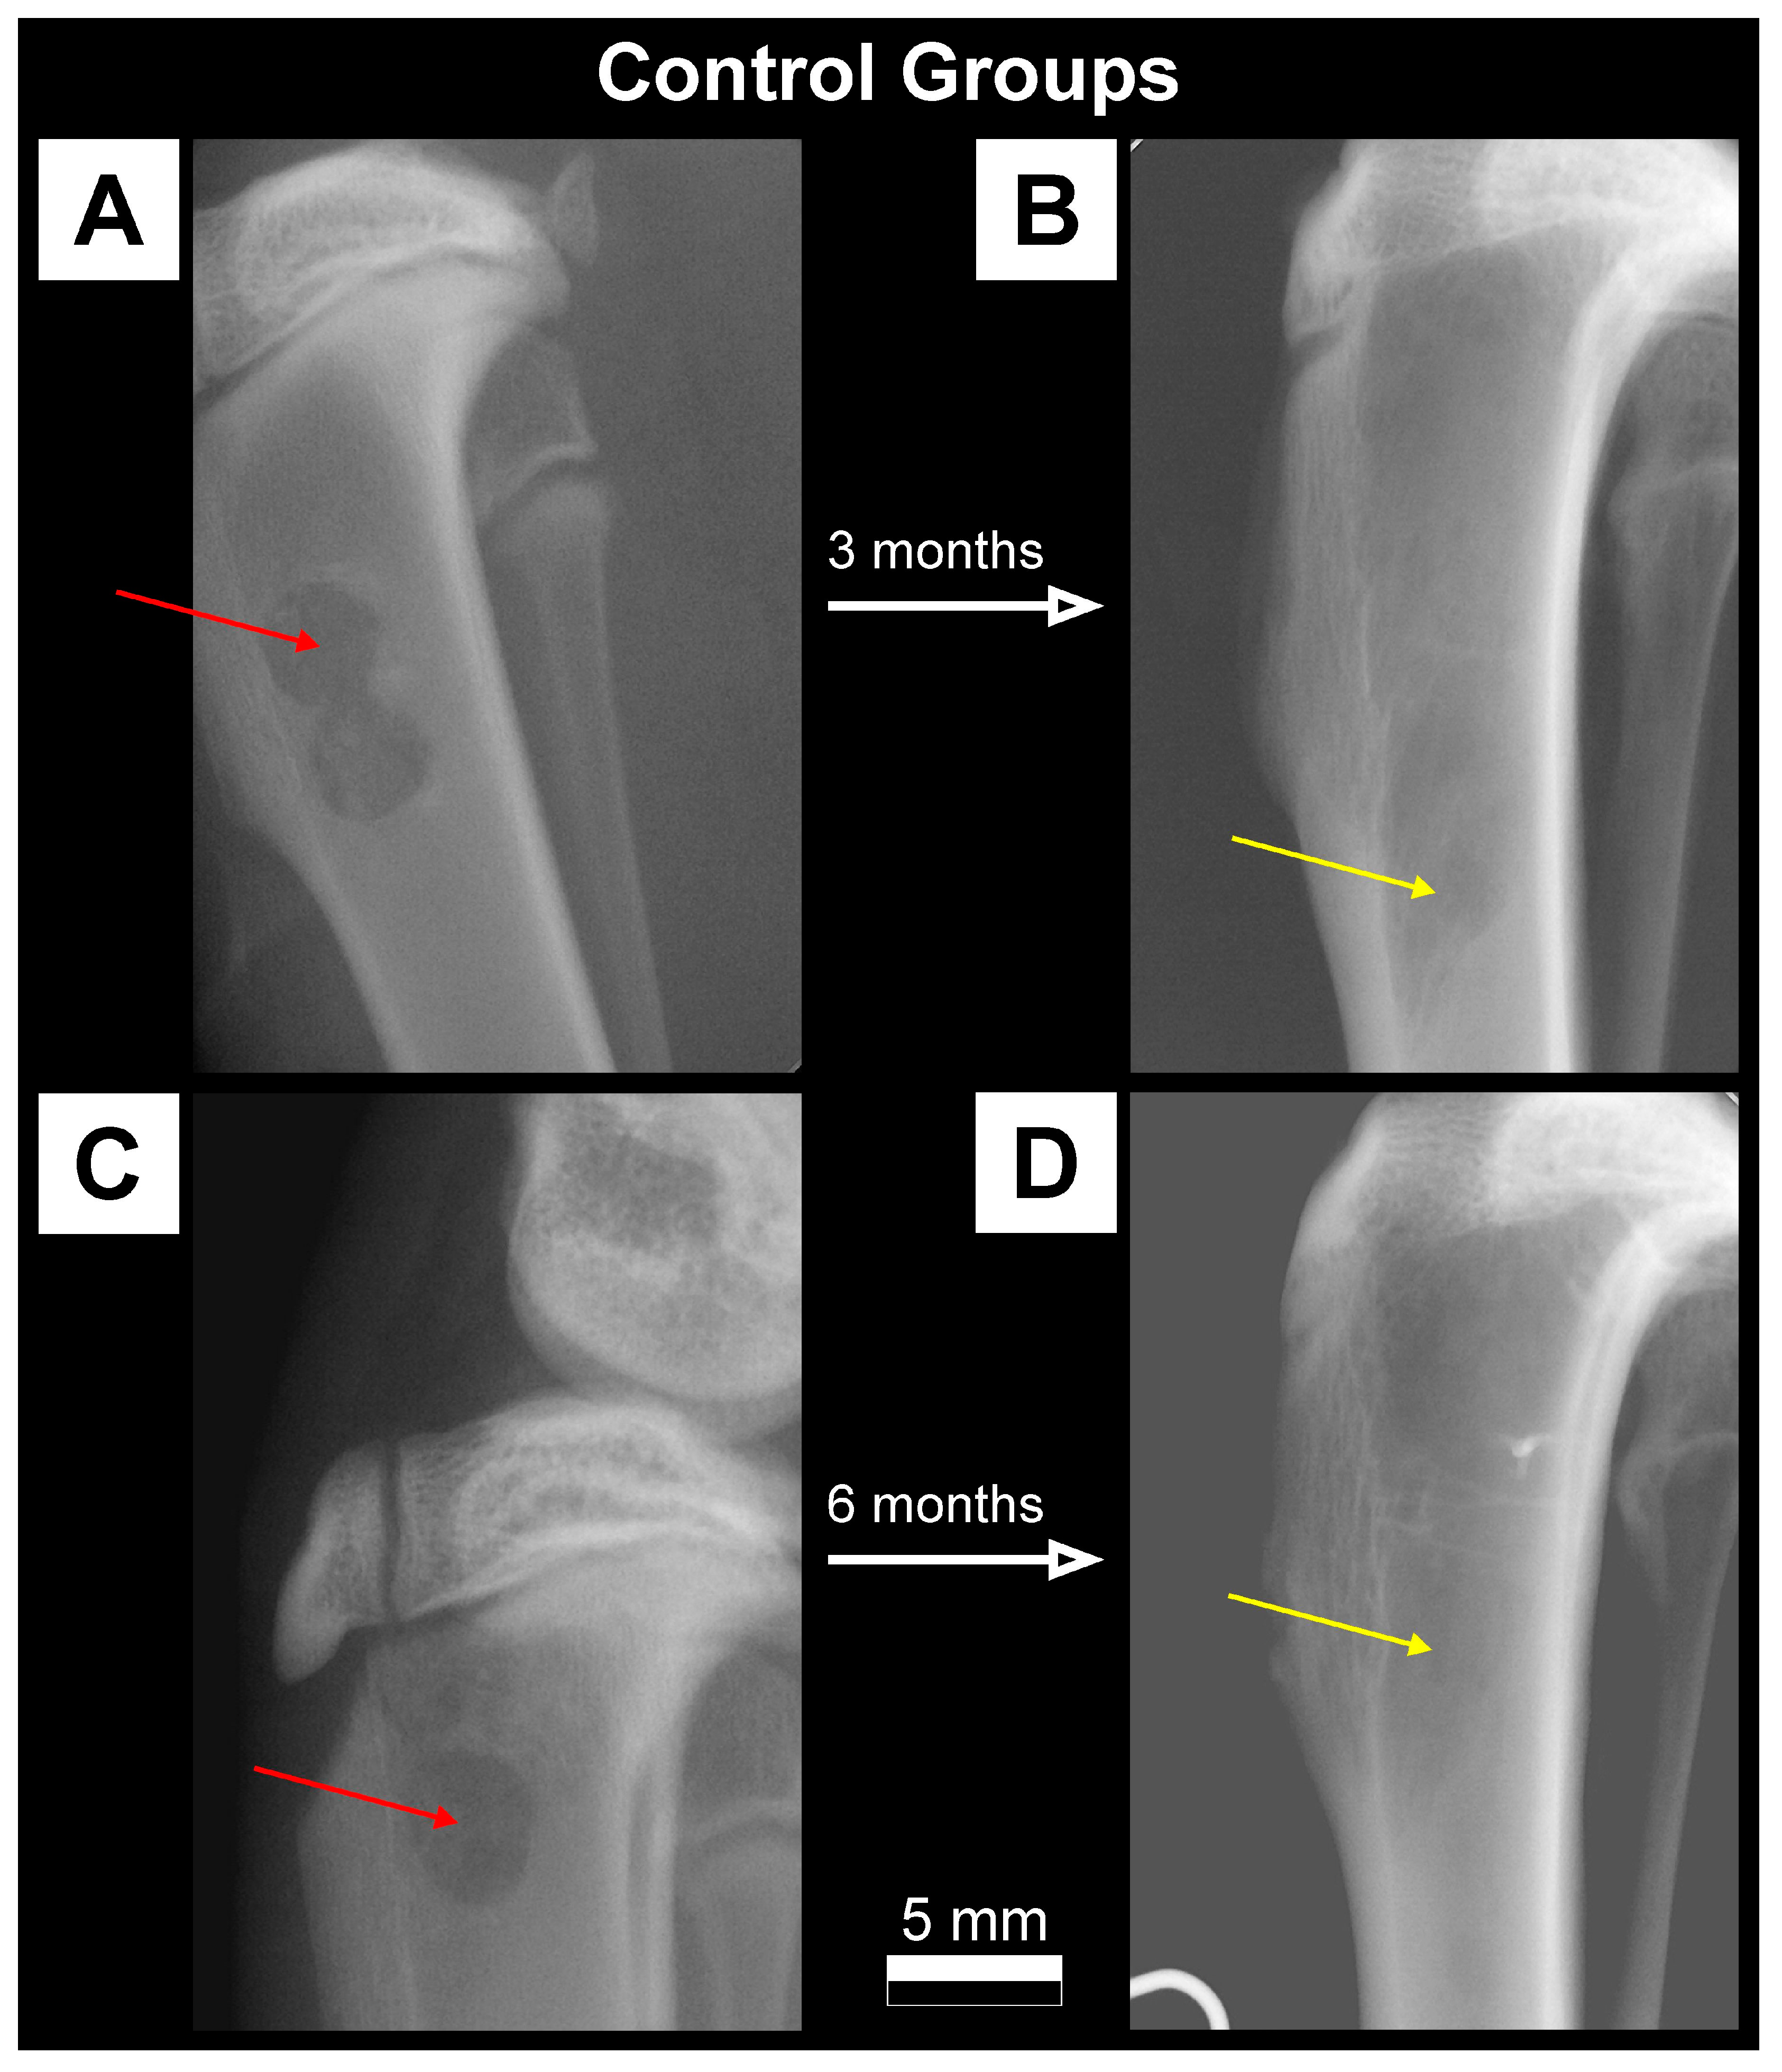

2.3.1. X-ray Imaging—Conventional Radiography

3.1. Qualitative Analysis of Bone Substitute Materials